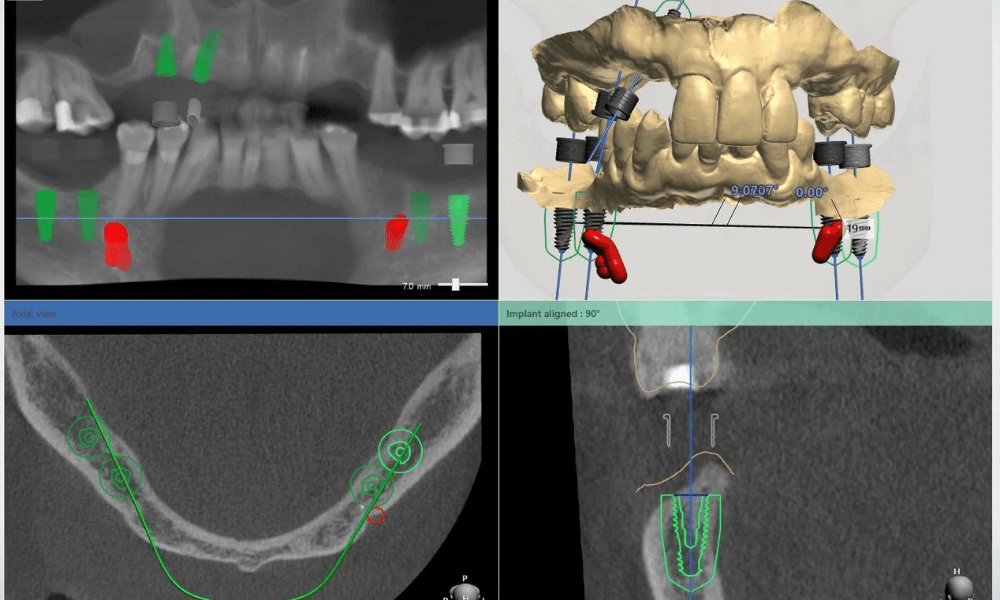

Công nghệ chẩn đoán: CT Cone Beam & phần mềm số hóa

Trong Implant hiện đại, chẩn đoán không còn dừng lại ở X-quang 2D mà phải sử dụng CT Cone Beam 3D để đánh giá toàn diện cấu trúc xương.

Công nghệ này cho phép:

- Đo chính xác chiều cao, chiều rộng và mật độ xương

- Xác định vị trí dây thần kinh hàm dưới

- Đánh giá nền xoang hàm trên

Kết hợp với phần mềm lập kế hoạch số hóa, bác sĩ có thể:

- Mô phỏng vị trí đặt trụ trước khi phẫu thuật

- Lựa chọn kích thước trụ phù hợp

- Tối ưu hướng cắm trụ để chịu lực tốt nhất